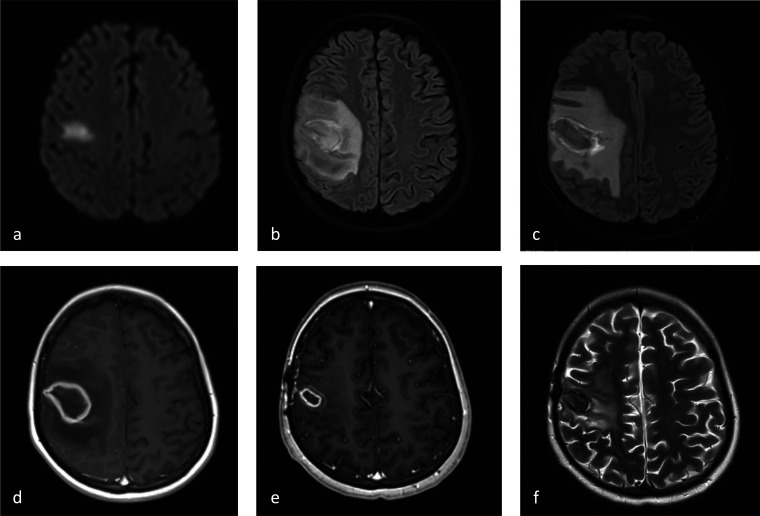

毛霉病是一种罕见的、危及生命的机会性感染,主要影响免疫功能低下的患者。关于儿童中枢神经系统(CNS)的pusillus (R pusillus)感染的现有文献非常有限。我们提出的情况下,免疫功能低下的青少年颅内毛霉病,由于R pusillus表现为中风样症状。该病例突出了这种罕见疾病的诊断复杂性和管理挑战。我们包括对现有文献的回顾小儿扁桃体中枢神经系统感染,以提高卫生保健提供者的认识。

Mucormycosis is a rare, life-threatening opportunistic infection primarily affecting immunocompromised patients. The available literature on Rhizomucor pusillus (R pusillus) infections of the central nervous system (CNS) in children is very limited. We present the case of an immunocompromised adolescent with intracranial mucormycosis due to R pusillus manifesting with stroke-like symptoms. This case highlights this rare condition's diagnostic complexity and management challenges. We include a review of the available literature on pediatric R pusillus CNS infections to increase awareness among health care providers.